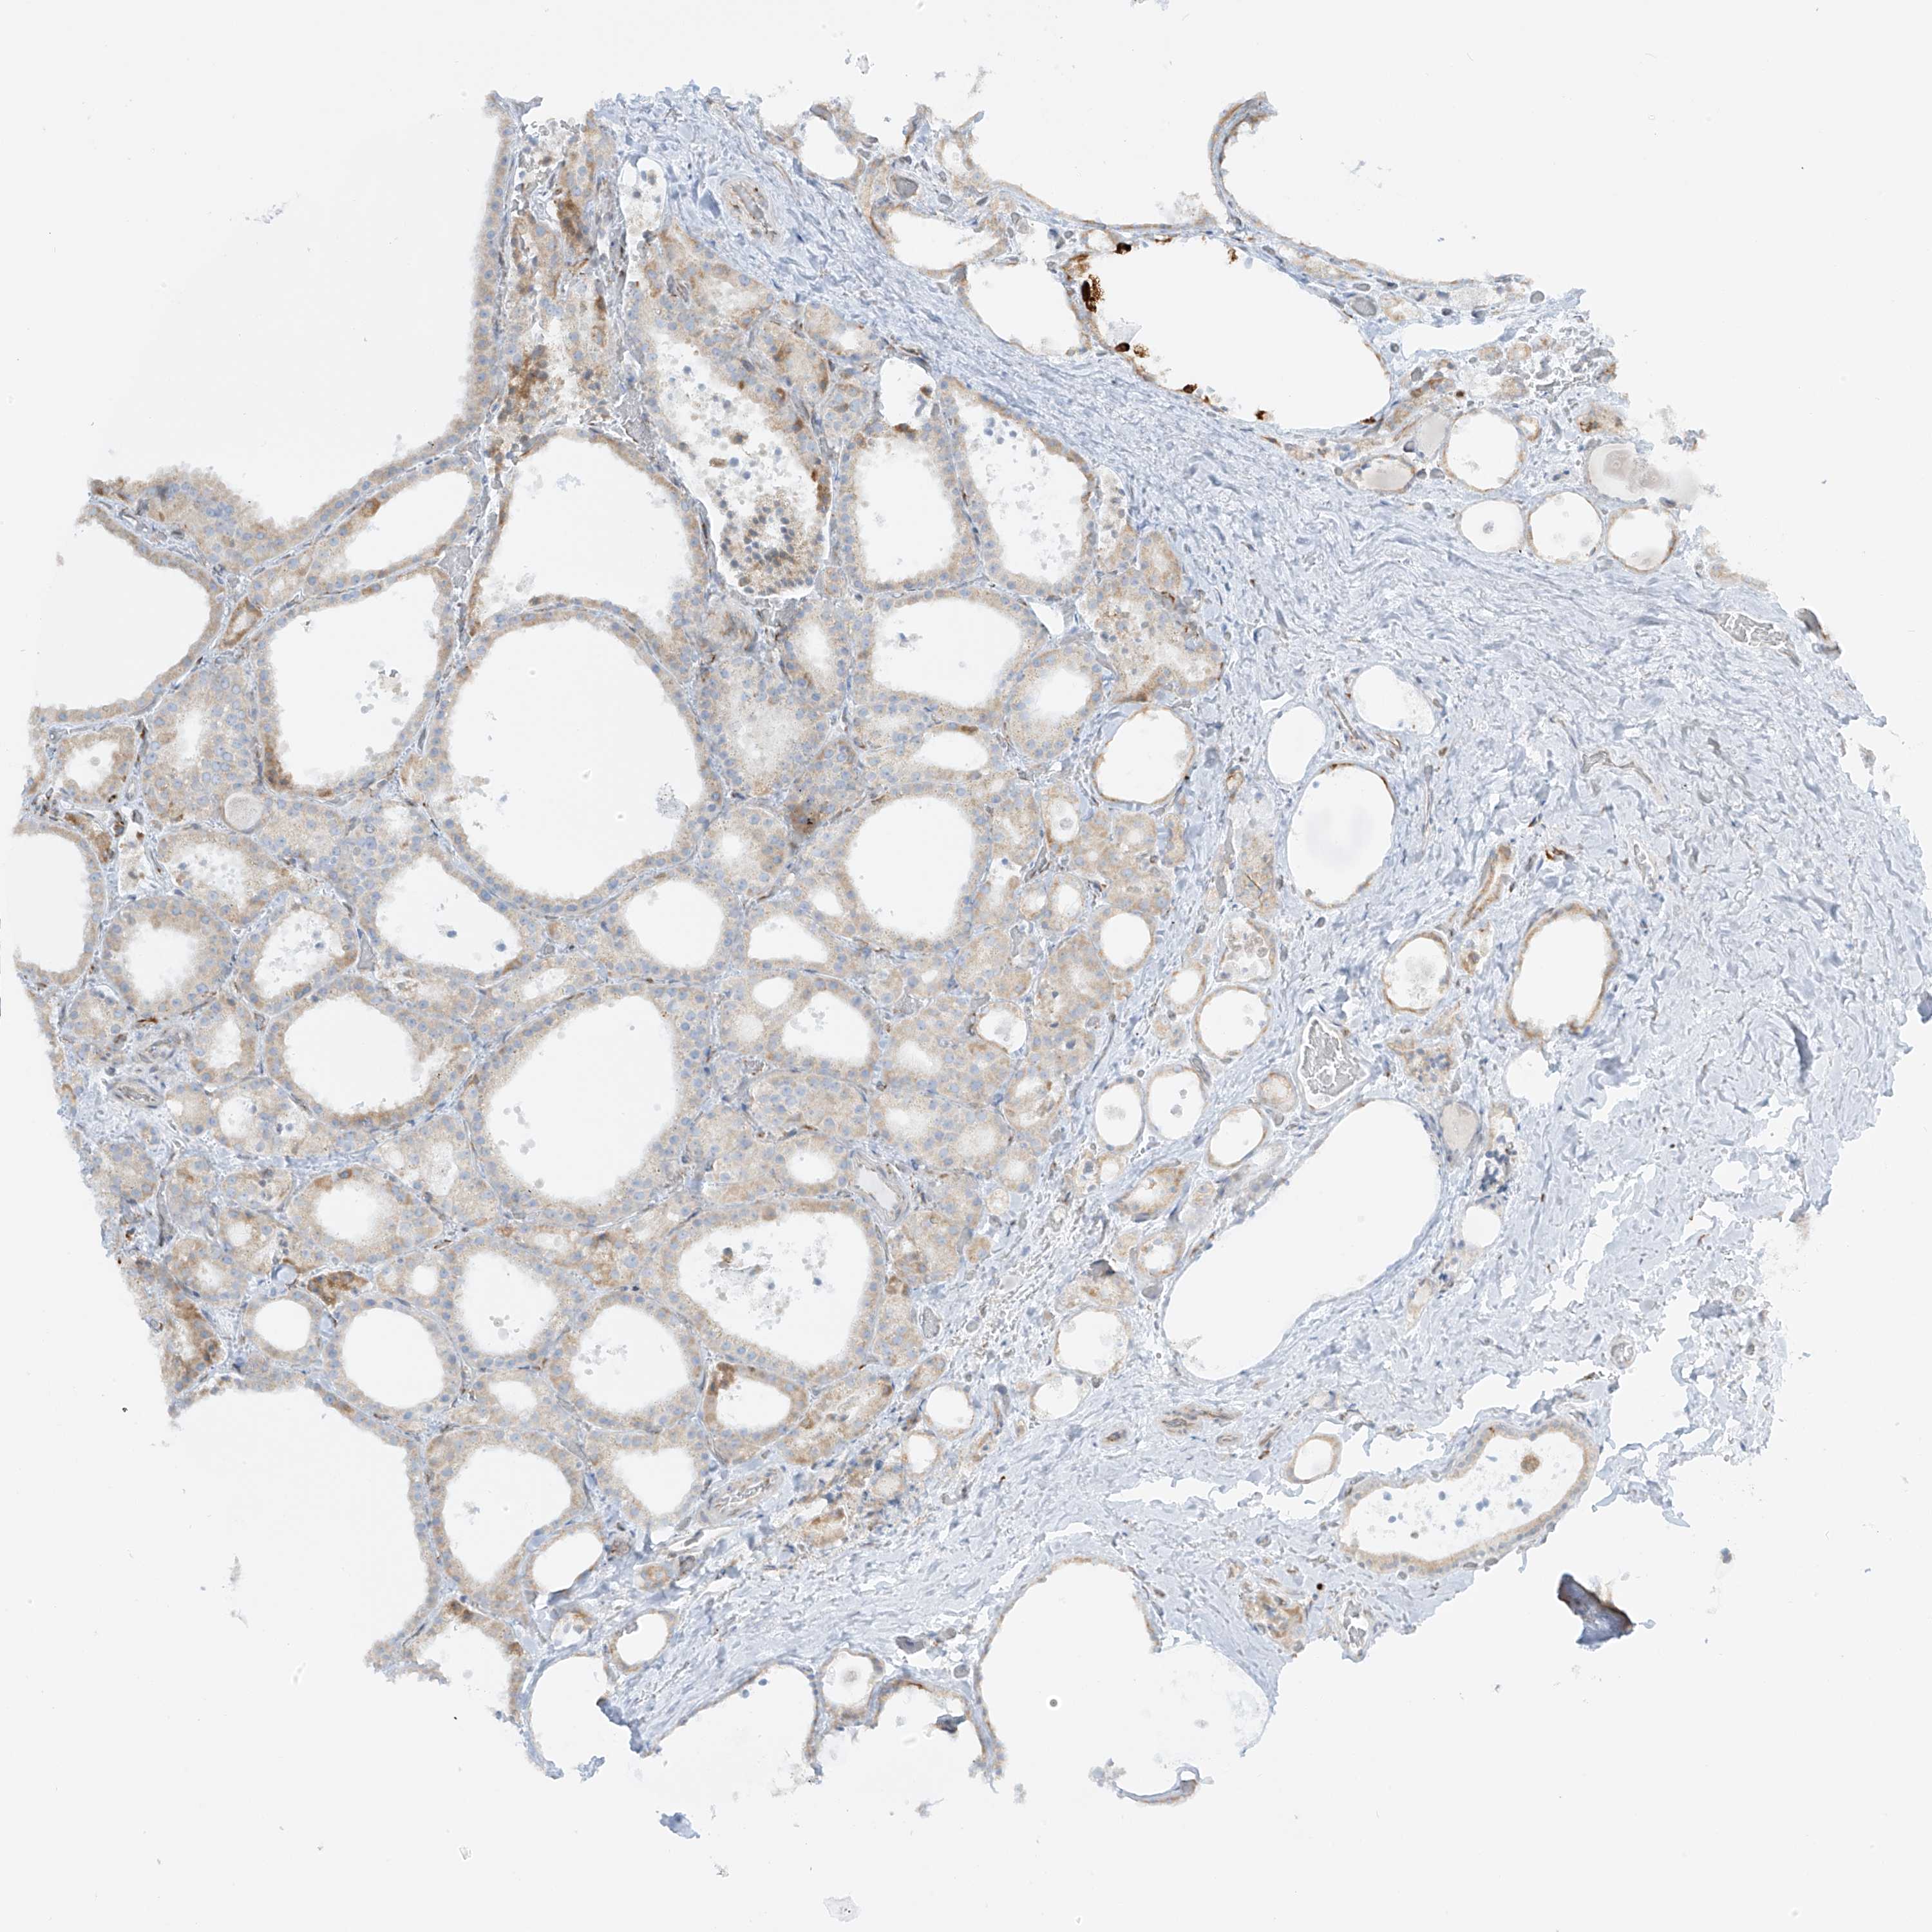

THYROID CANCER - Protein expressioni

A mouse-over function shows sample information and annotation data. Click on an image to view it in a full screen mode. Samples can be filtered based on level of antibody staining by selecting one or several of the following categories: high, medium, low and not detected. The assay and annotation is described here.

Note that samples used for immunohistochemistry by the Human Protein Atlas do not correspond to samples in the TCGA dataset.

Antibody stainingi

Antibody staining in the annotated cell types in the current human tissue is reported as not detected, low, medium, or high, based on conventional immunohistochemistry profiling in selected tissues. This score is based on the combination of the staining intensity and fraction of stained cells.

Each image is clickable and will lead to virtual microscopy that enables deeper exploration of all samples and also displays staining intensity scores, fraction scores and subcellular localization as well as patient and tissue information for each sample.

Antibody HPA030827

Antibody HPA030829

Staining

High

Medium

Low

Not detected

Intensity

Strong

Moderate

Weak

Negative

Quantity

>75%

75%-25%

<25%

None

Location

Nuclear

Cytoplasmic/membranous

Cytoplasmic/membranous,nuclear

Papillary adenocarcinoma, NOS

Follicular adenoma carcinoma, NOS